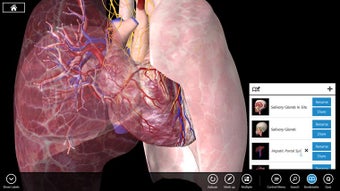

Essential Anatomy 3 bukanlah revolusi dalam rangkaian aplikasi Essential Anatomy tetapi menambahkan lebih banyak detail dan kemudahan penggunaan ke aplikasi. Hal yang paling mengesankan tentang Essential Anatomy 3 adalah tingkat detail dan model 3D yang dapat Anda manipulasi dan jelajahi. Essential Anatomy 3 tidak meninggalkan organ atau tendon terbuka - tingkat detailnya sama bagusnya dengan apa pun yang Anda temukan di Ensiklopedia medis.

Untuk mahasiswa kedokteran khususnya, Essential Anatomy adalah alat referensi yang luar biasa. Model 3D memungkinkan Anda untuk melihat dan memeriksa bagian tubuh manusia dari sudut mana pun memberikan detail luar biasa yang biasanya hanya dapat Anda alami melalui pembedahan.

Jika Anda perlu menemukan tulang, organ tertentu atau otot, Anda cukup menelusuri berdasarkan bagian tubuh dan Essential Anatomy akan menyorot dengan tepat di mana mereka berada dengan deskripsi bermanfaat dari setiap bagian. Satu-satunya hal yang kurang adalah animasi organ dan otot yang sedang beraksi.